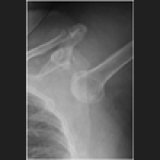

Joint Dislocation is the complete dissociation of the articulating surfaces of a joint. While a Subluxation is when the articulating surfaces of a joint remain ...